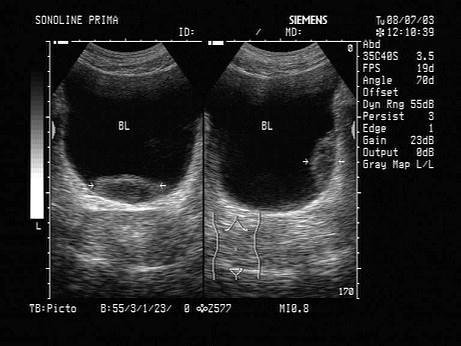

问题 根据超声图像,该病例最可能诊断为?(?)

选项 A.膀胱结石 B.膀胱血块 C.膀胱异物 D.膀胱肿瘤 E.腺性膀胱炎

答案 B